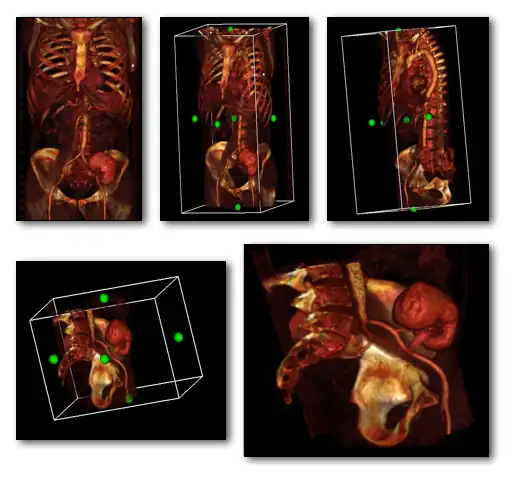

The final image processing step is to volume render this difference stack along with the "pure perfusion" scan and to blend the results, as illustrated in the following image:

The steps involved are outlined in the following diagram. Note that minor processes, such as CLUT selection, relative opacity adjustment and contrast enhancement are omitted from this diagram for the sake of simplicity. Note also that an image registration step may need inclusion at the beginning of the procedure in cases where patient movement occurs between the two SPECT acquisitions.

A final point to note is the larger appearance of the patient's lungs in the segmented CTPA images relative to the SPECT images. This arises because the CTPA study was acquired using a single breath-hold and the SPECT studies with the patient breathing quietly over the period of gamma camera rotation. The spatial registration of the three sets of images is therefore not possible directly, and would require the application of spatial warping and other techniques which, unfortunately, are beyond the scope of our treatment here.